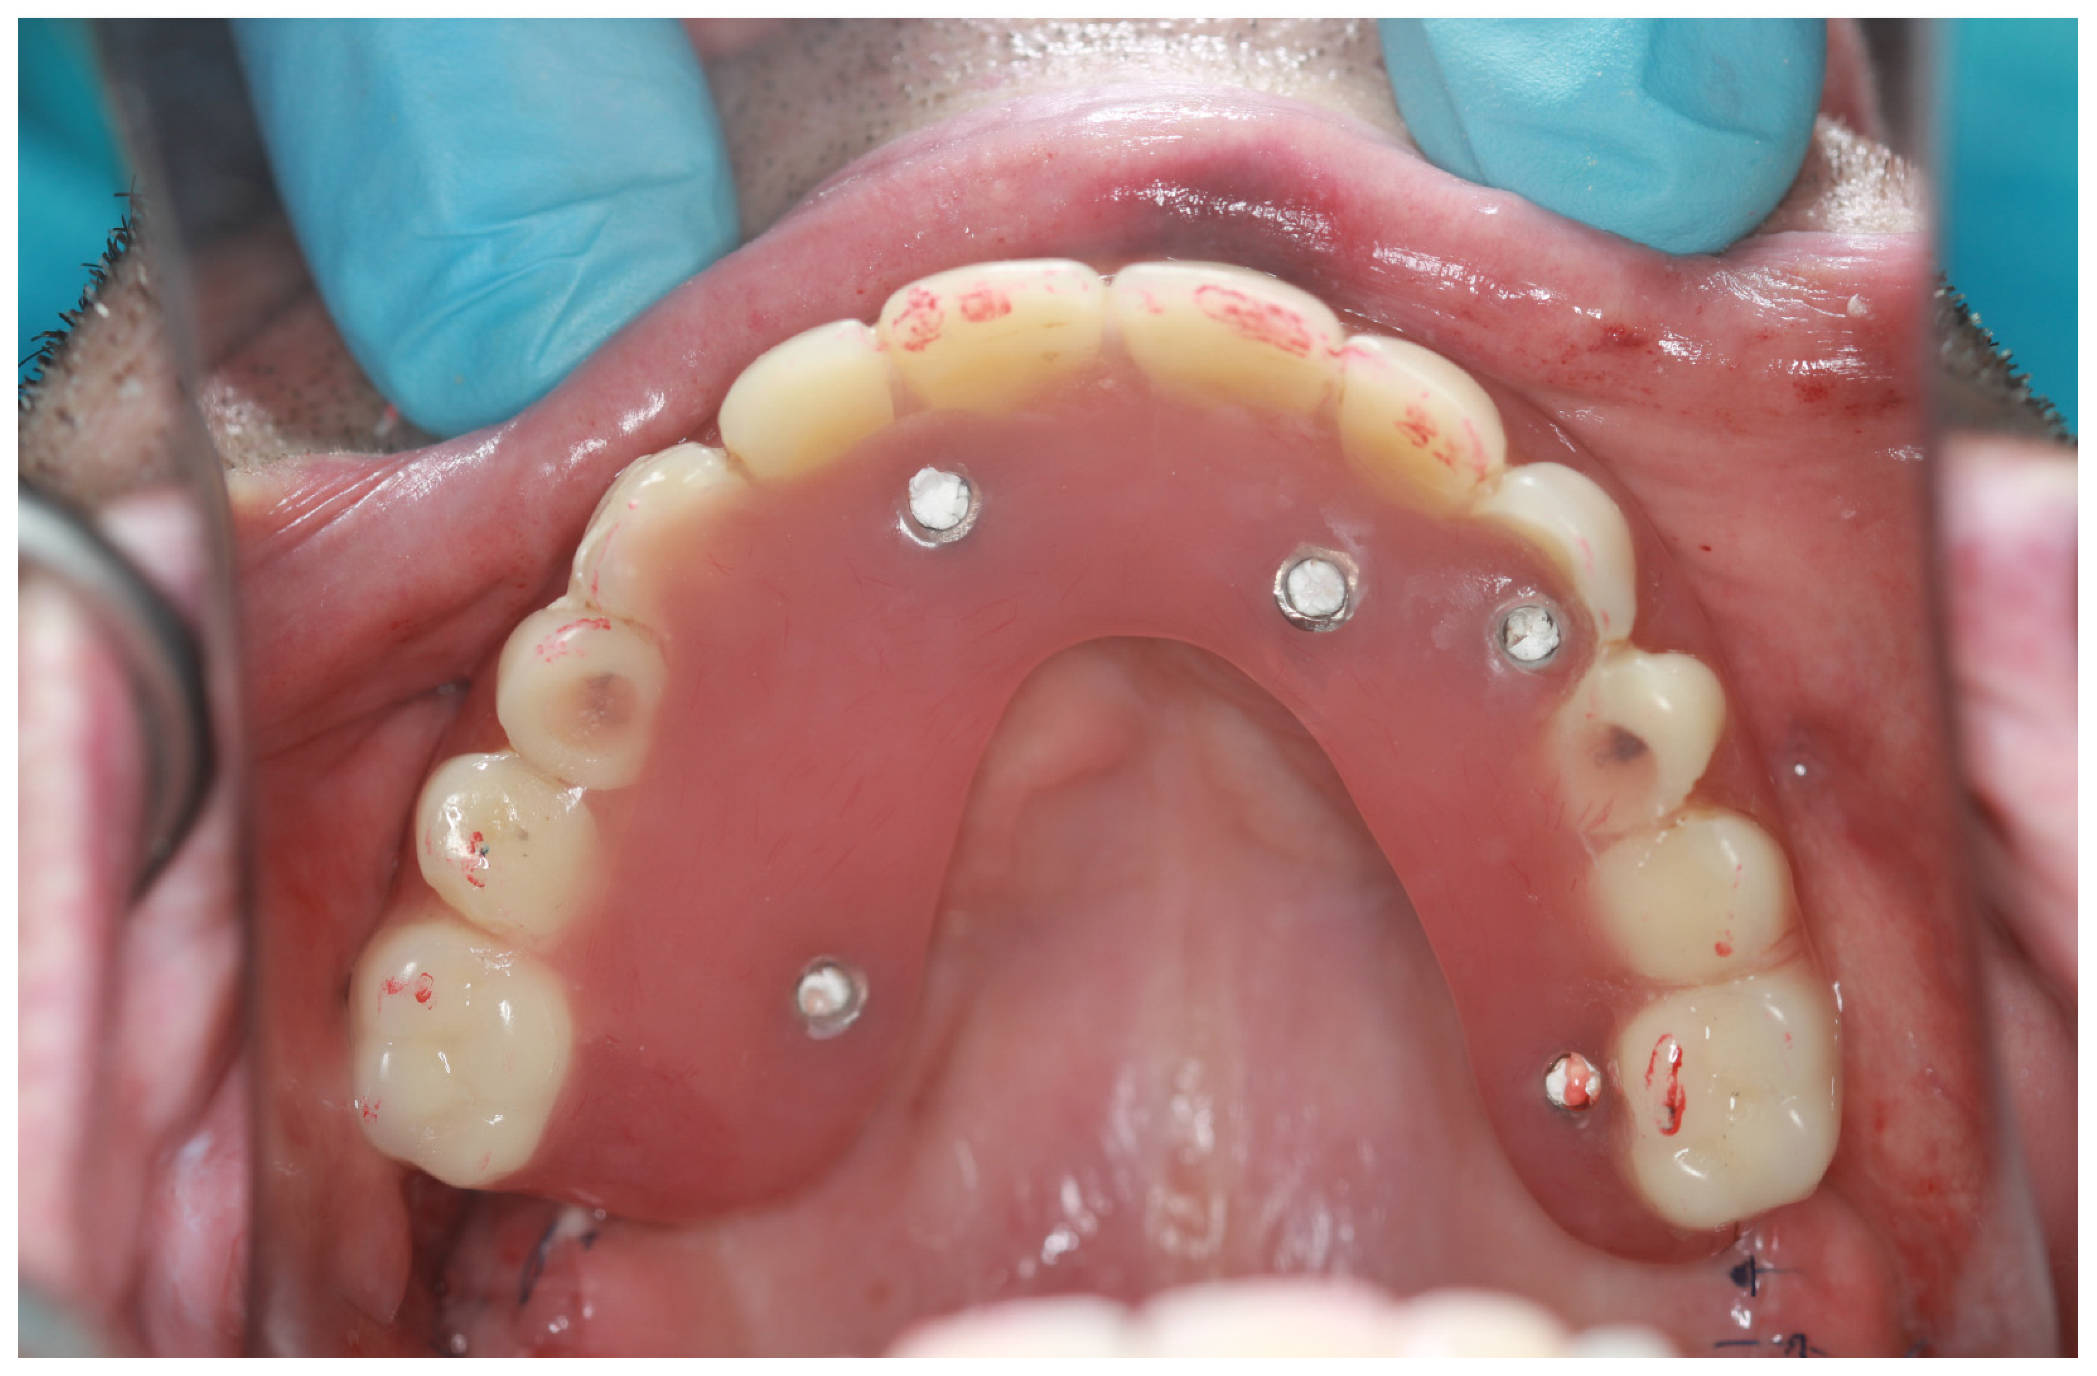

2. Materials and Methods

2.2. Surgery